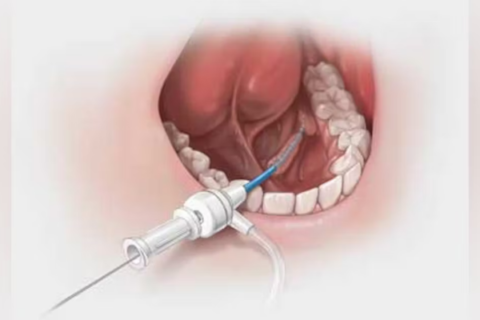

Salivary Gland Surgeries

Treating blockages, stones, or tumors of salivary glands.